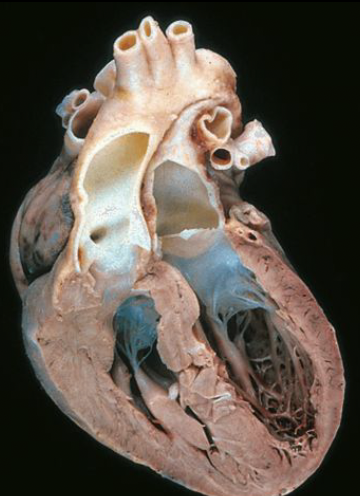

VSD

pulmonary stenosis

right ventricular hypertrophy

overriding aorta

tetralogy of fallot (TOF)